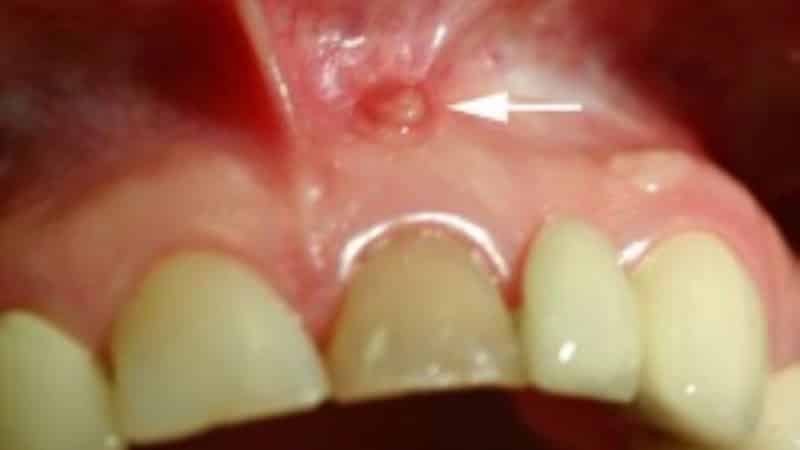

К основным симптомам воспалительных процессов, вызванных некачественной подготовкой, относятся зубная боль, образование флюса, отек десен, свищи и кисты. Боль в зубе под коронкой возникает из-за развития периодонтита в верхушке корня, что приводит к образованию гноя. Это вещество давит на ткани, вызывая боль. Хроническое воспаление может проявляться периодическими болями. Свищи формируются после острых воспалений с отеками десен и щек, соединяя полость рта с областью гноя тонким проходом. Образование флюса также указывает на воспаление верхушки корня, что сопровождается болью, отеком и подвижностью зуба. Хронический периодонтит в тяжелой форме может приводить к образованию кисты в области верхушки корня.

Киста может проявляться периодической припухлостью десны в месте больного зуба, но иногда не дает никаких признаков или со временем увеличивается. Определить наличие кисты можно с помощью рентгеновского снимка.